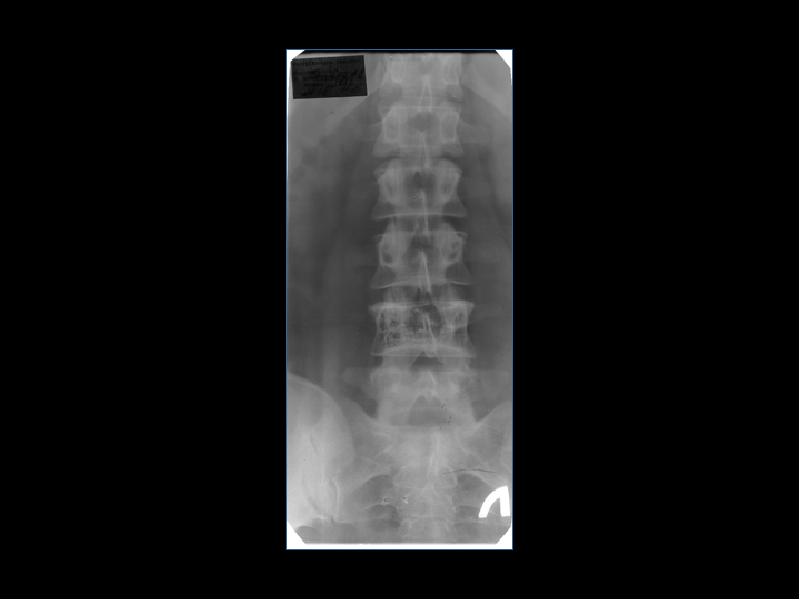

Лучевая диагностика доброкачественных